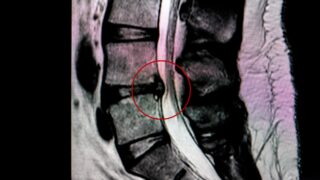

まず理解しておきたいのは、レントゲンやMRIはとても優れた検査ですが、すべての痛みの原因を映し出せるわけではないということです。

レントゲンやMRIで主に確認できるのは次のようなものです。

・椎間板ヘルニア

・脊柱管狭窄

・骨の変形

・炎症や腫瘍

このように、比較的大きな構造の変化を確認することは得意です。

しかし慢性的な腰痛の多くは、こうしたはっきりした構造の異常と一致しないことが多いといわれています。

研究では、腰痛のない人でもヘルニアや椎間板の変性が見つかることが珍しくないことも分かっています。

こうした変化はMRIではほとんど映りません。